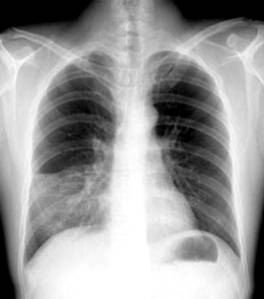

照片名称:正常胸片